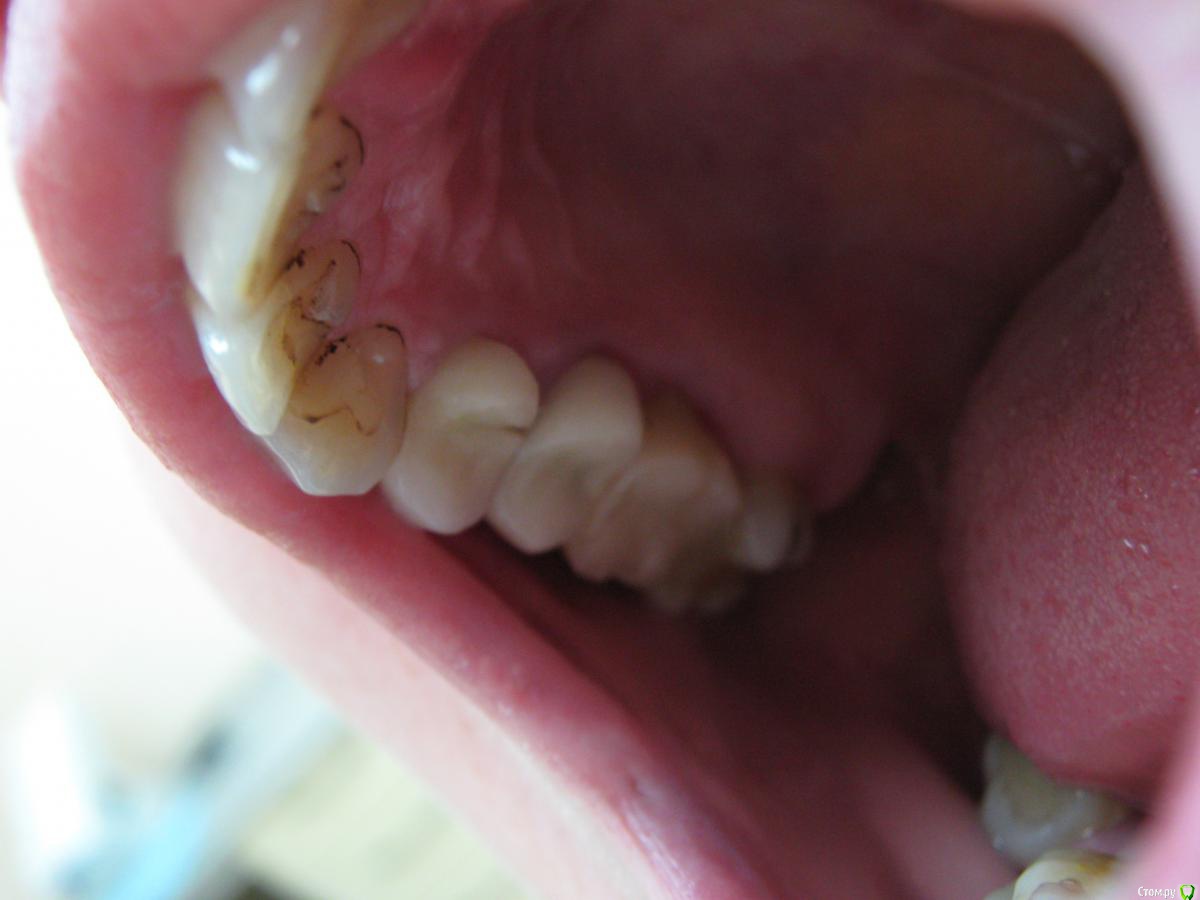

Кирилл 1986 Опубликовано 8 февраля, 2016 Поделиться Опубликовано 8 февраля, 2016 Цельнокерамические коронки на 14,15 зубах (Duceram Kiss на огнеупорной модели), поставлены чуть больше года назад, прилегание коронок сохранено,без изменений, окклюзионная схема тоже. Скол в фиссуре,на всю толщину коронки, произошёл со слов пациента при жевании яблока, скорее всего одним куском ( керамики). При жевании ничего не мешало, зубочистками пациент не пользовался. Какие могут быть причины скола? Что учесть при замене коронки? Ссылка на комментарий